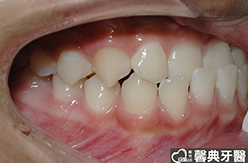

患者︰黃小弟弟,十三歲,學生。

主訴︰戽斗,想做矯正。

治療計劃︰上顎前牙排齊後彈出,下顎前牙排齊後後縮,重建正常咬合關係。